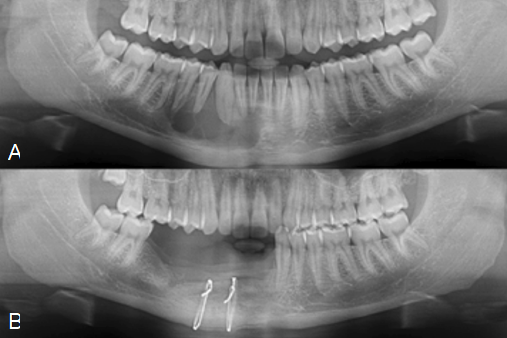

. Journey of okc from cyst to tumor to cyst again. Implant surgery for the placement of dental implants is performed after full bony consolidation of the bone grafts to complete full oral rehabilitation for the patient. Biopsy results came back positive with the diagnosis of odontogenic keratocyst in the left mandibular region.

There was a recurrence of the cyst in a few months and. Odontogenic keratocyst okc or keratocystic odontogenic tumor kcot. Large odontogenic keratocysts sometimes are treated initially by cystotomy and insertion of a drainage tube which can promote shrinkage of the lesion and fibrous thickening of the cyst wall before subsequent total removal.

CT scans in axial and coronal planes. Long-term follow-up with monitoring by X-ray is important as if these cysts are left untreated they can become quite large and locally destructive. We recommend the following protocol in the management of large mandibular OKC.

Surgical Removal of Odontogenic Keratocyst. Odontogenic keratocysts OKCs are benign intraosseous odontogenic lesions that have a locally aggressive behavior and exhibit a high recurrence rate after the treatment. Odontogenic keratocysts can initially be treated with incisional biopsy and decompression by installing a polyethylene drain to allow subsequent reduction of the cystic cavity size resulting in thickening of the capsule which allows a later easy removal withapparently lower relapse rate waldron.

Conservative Management Of Odontogenic Keratocyst With Long Term 5 Year Follow Up Case Report And Literature Review Sciencedirect

Treatment With Decompression Of An Odontogenic Keratocyst